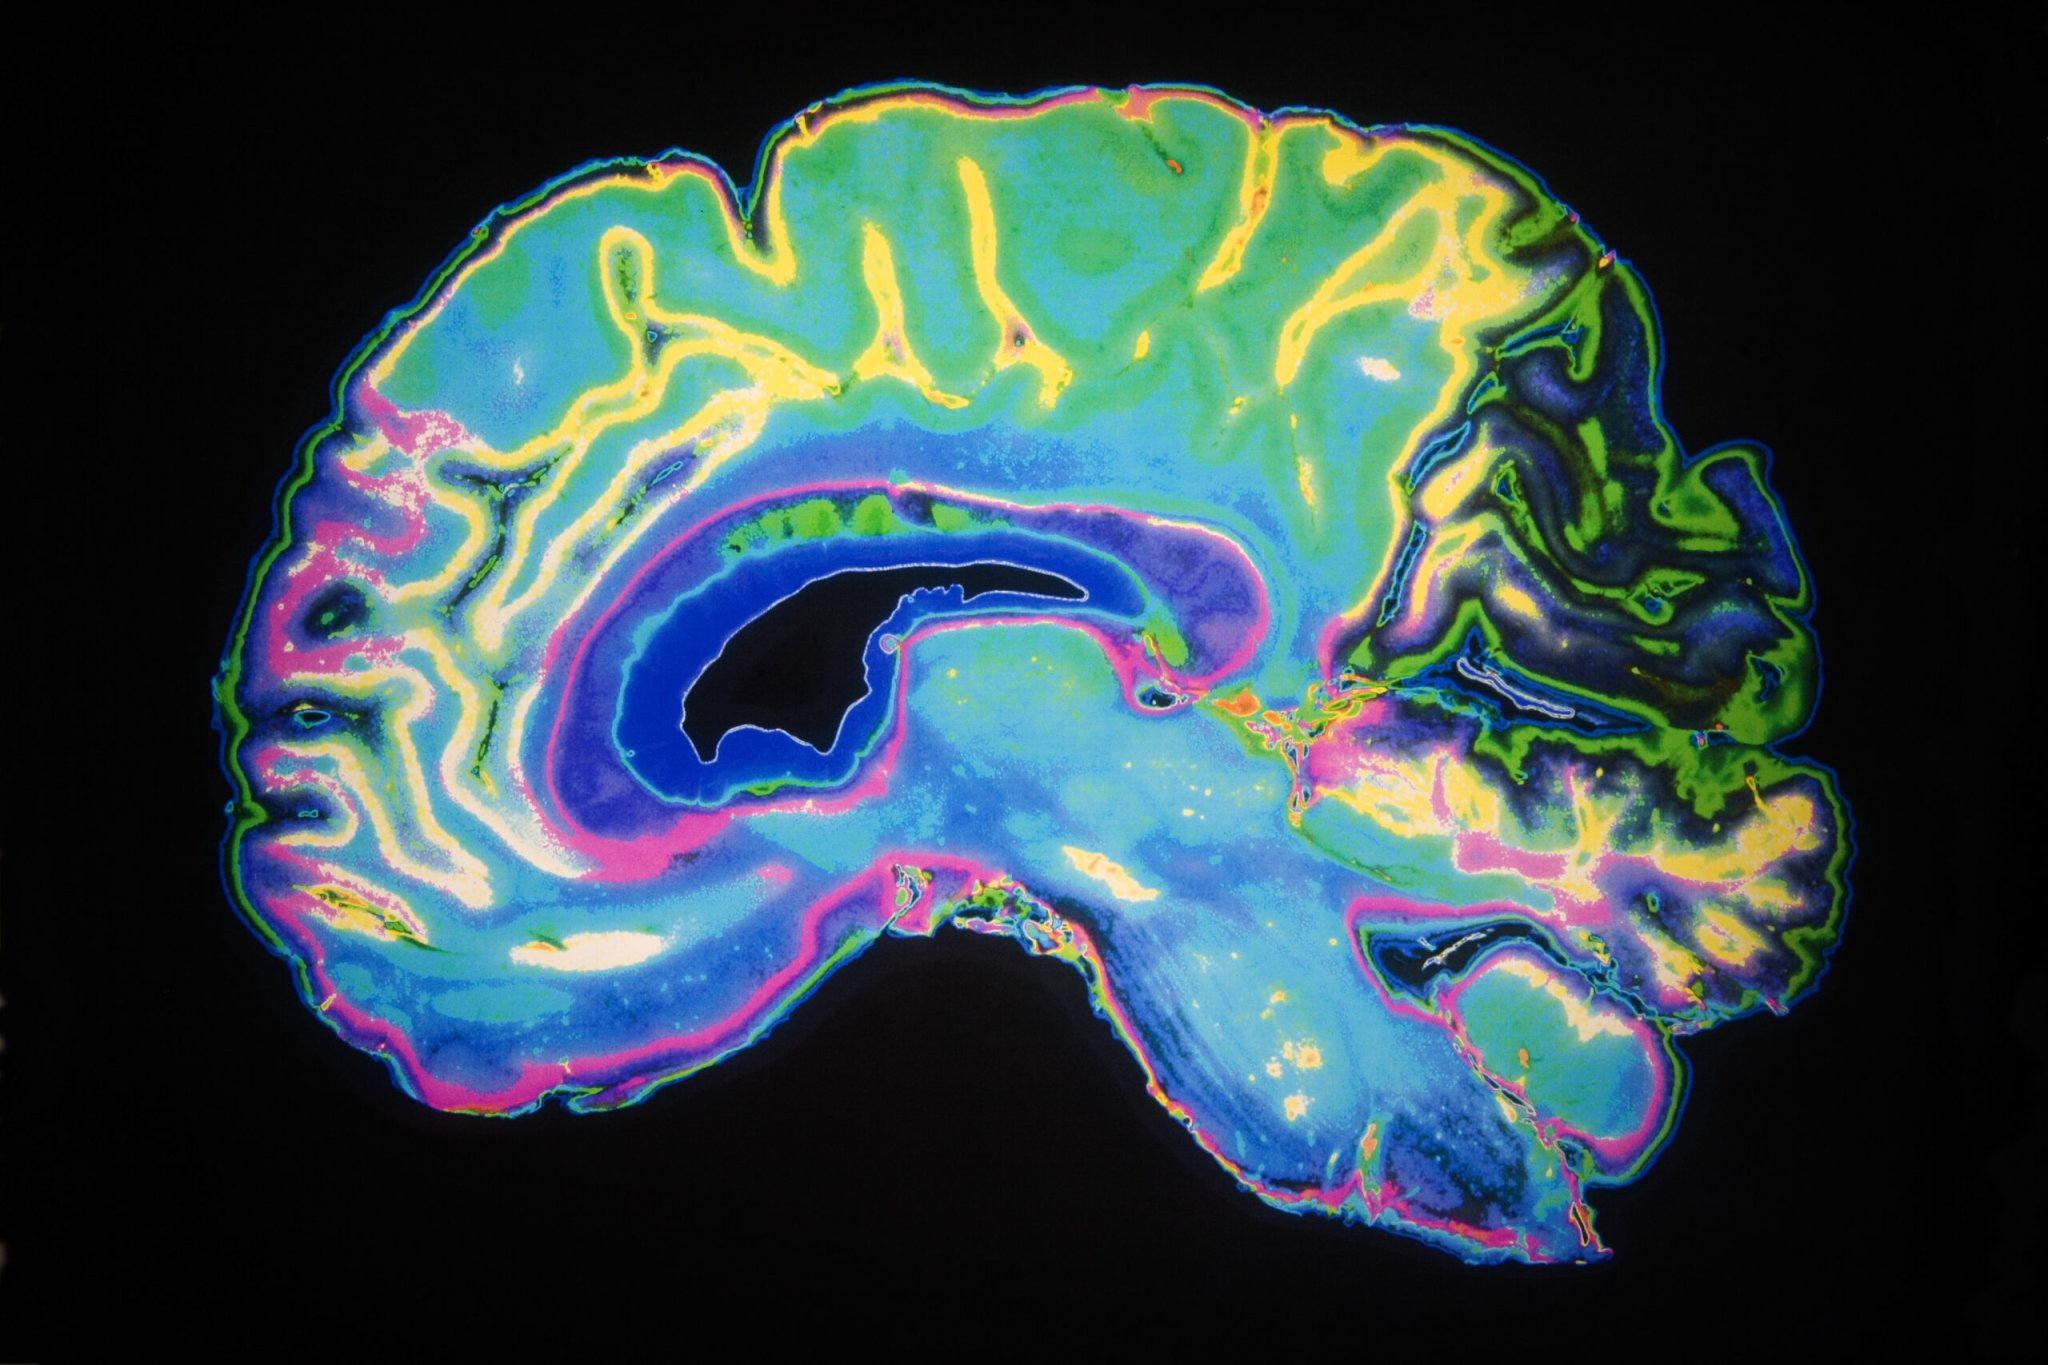

Vaghi and her collaborators are planning to look at the brain activity of people with OCD during the ball and basket task, in an attempt to pinpoint the regions of the brain involved in this particular dysfunctional activity. “Our hypothesis that the frontal striatal lobes are involved,” she says.

Vaghi’s overall goal is to help reduce stigma around mental illness, by identifying the physical roots of psychological problems. “I’d like everyone to know if you have mental illness it’s because you have a problem with your brain.”